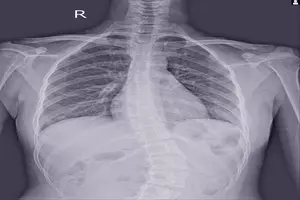

척추측만증은 흔한 질환으로, 척추가 옆으로 휘어지는 것을 의미합니다. 정상적인 척추는 S자 모양으로 약간 구부려져 있지만, 측만증 환자의 경우 이 구부러짐이 10도 이상 심각해집니다. 척추측만증은 누구에게나 발생할 수 있지만, 청소년기에 더 흔합니다. 오늘은 이를 위해 척추측만증 치료법, 증상, 원인, 수술에 대해 알아보도록 하겠습니다.

척추측만증은 척추가 옆으로 휘어지는 척추 기형입니다. 약 100명 중 3~4명이 척추측만증을 가지고 있으며, 대부분의 경우 어린 시기에 발병합니다. 이는 단순한 측만뿐만 아니라, 척추뼈 자체의 회전 변형을 동반하기 때문에 3차원적인 기형 상태라고 볼 수 있습니다. 척추측만증은 심각한 경우 호흡 곤란, 심장 질환, 통증 등의 건강 문제를 일으킬 수 있지만, 조기 발견 및 치료를 통해 정상적인 삶을 살 수 있습니다.

가장 흔한 증상이며, 측면에서 봤을 때 척추가 C자 또는 S자 형태로 휘어져 있는 모습으로 나타납니다. 경미한 경우 눈에 잘 띄지 않을 수 있지만, 진행될수록 척추 왜곡이 심해져 뚜렷하게 드러납니다. 일반적으로 10도 이상의 측만 되면 척추측만증으로 진단됩니다.